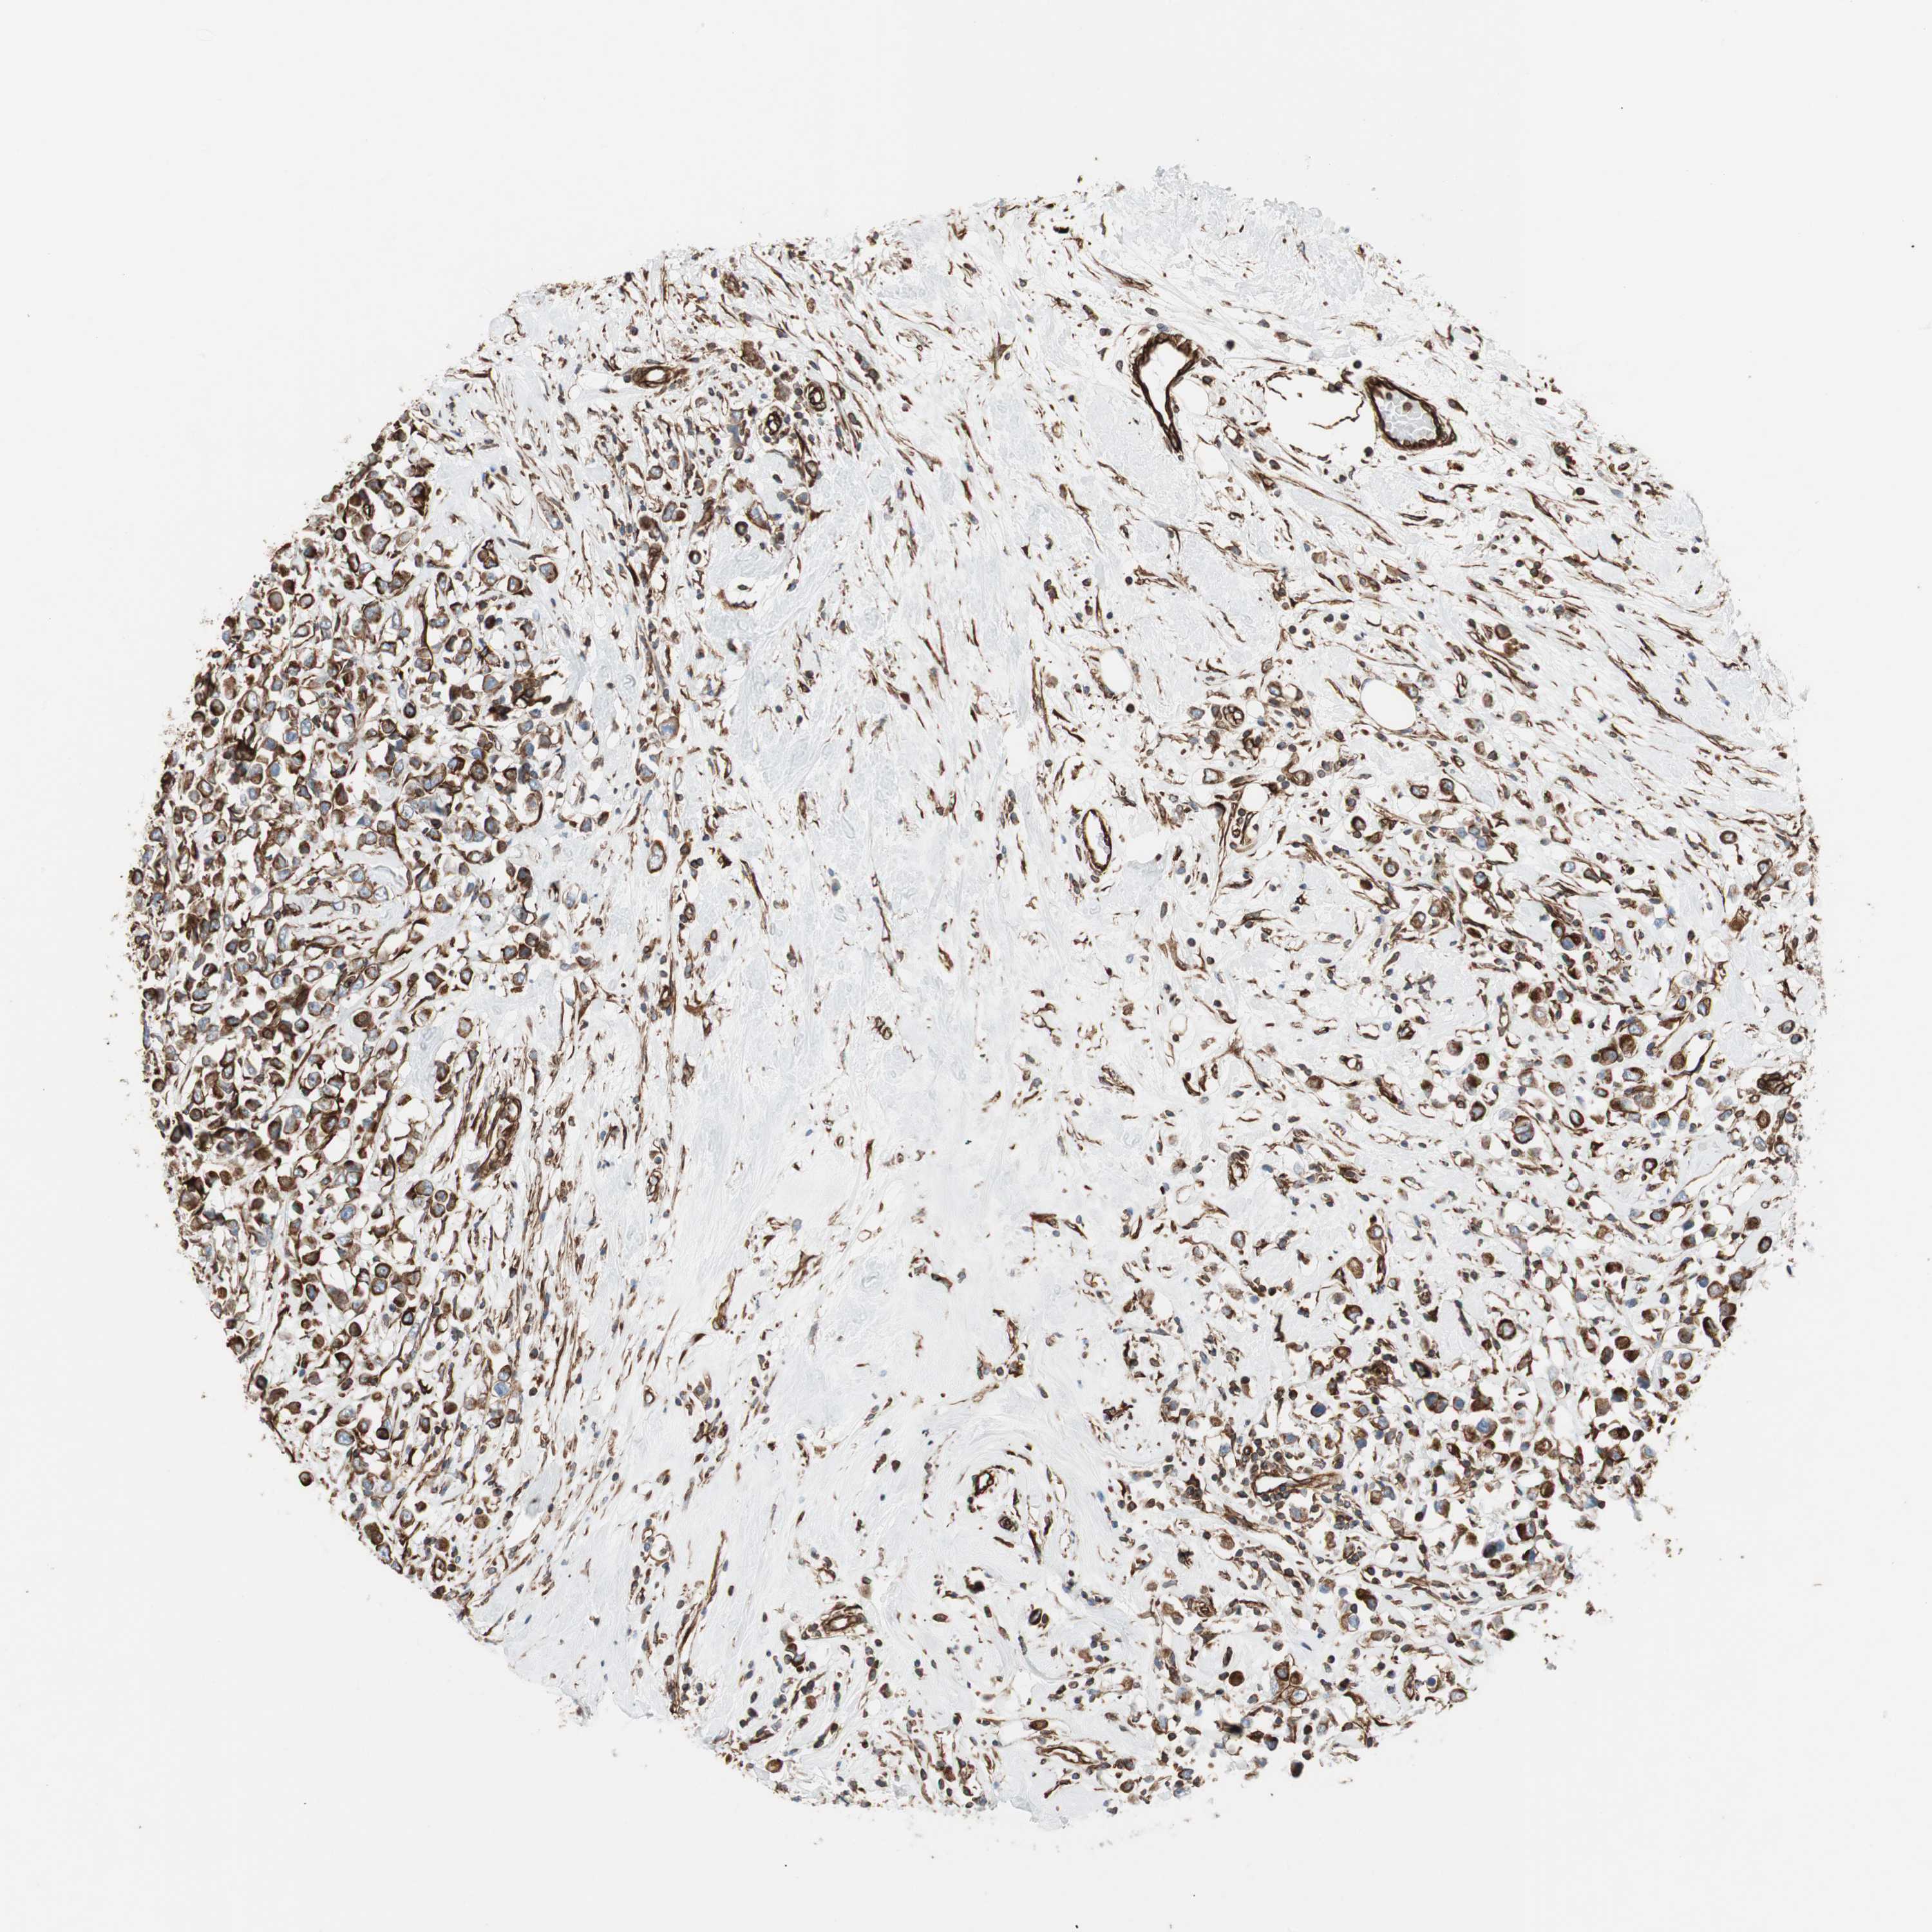

CANCER BREAST CANCER Show tissue menu

BRCA TCGA BRCA VALIDATION PROTEIN EXPRESSION